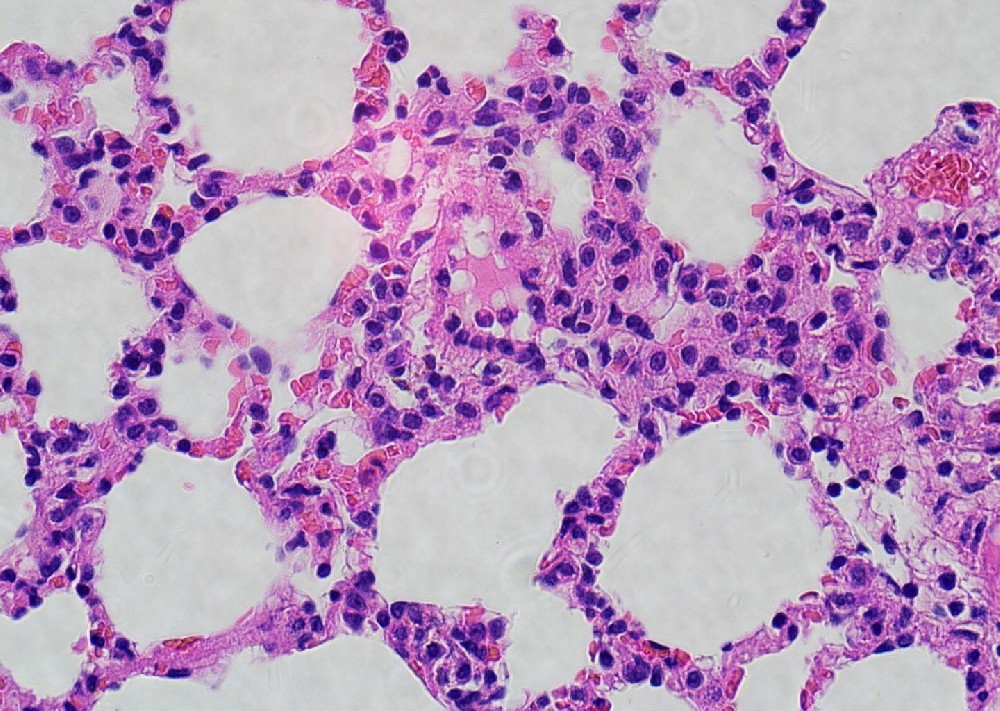

南京微眾生物科技有限公司是一家專業(yè)從事病理學(xué)研究及檢測(cè)技術(shù)服務(wù)的高科技公司,現(xiàn)已搭建國(guó)際前沿的病理學(xué)研究技術(shù)平臺(tái),包括普通病理實(shí)驗(yàn)室、分子病理實(shí)驗(yàn)室、超微病理實(shí)驗(yàn)室以及科研技術(shù)服務(wù)平臺(tái)。公司匯聚國(guó)內(nèi)外深耕病理學(xué)研究領(lǐng)域數(shù)十載的專家團(tuán)隊(duì),以標(biāo)準(zhǔn)化、系統(tǒng)化的項(xiàng)目管理流程,為制藥企業(yè)、科研院所等客戶提供專業(yè)的病理檢測(cè)技術(shù)服務(wù),助力生命健康領(lǐng)域從基礎(chǔ)研究到產(chǎn)業(yè)化的加速轉(zhuǎn)化。